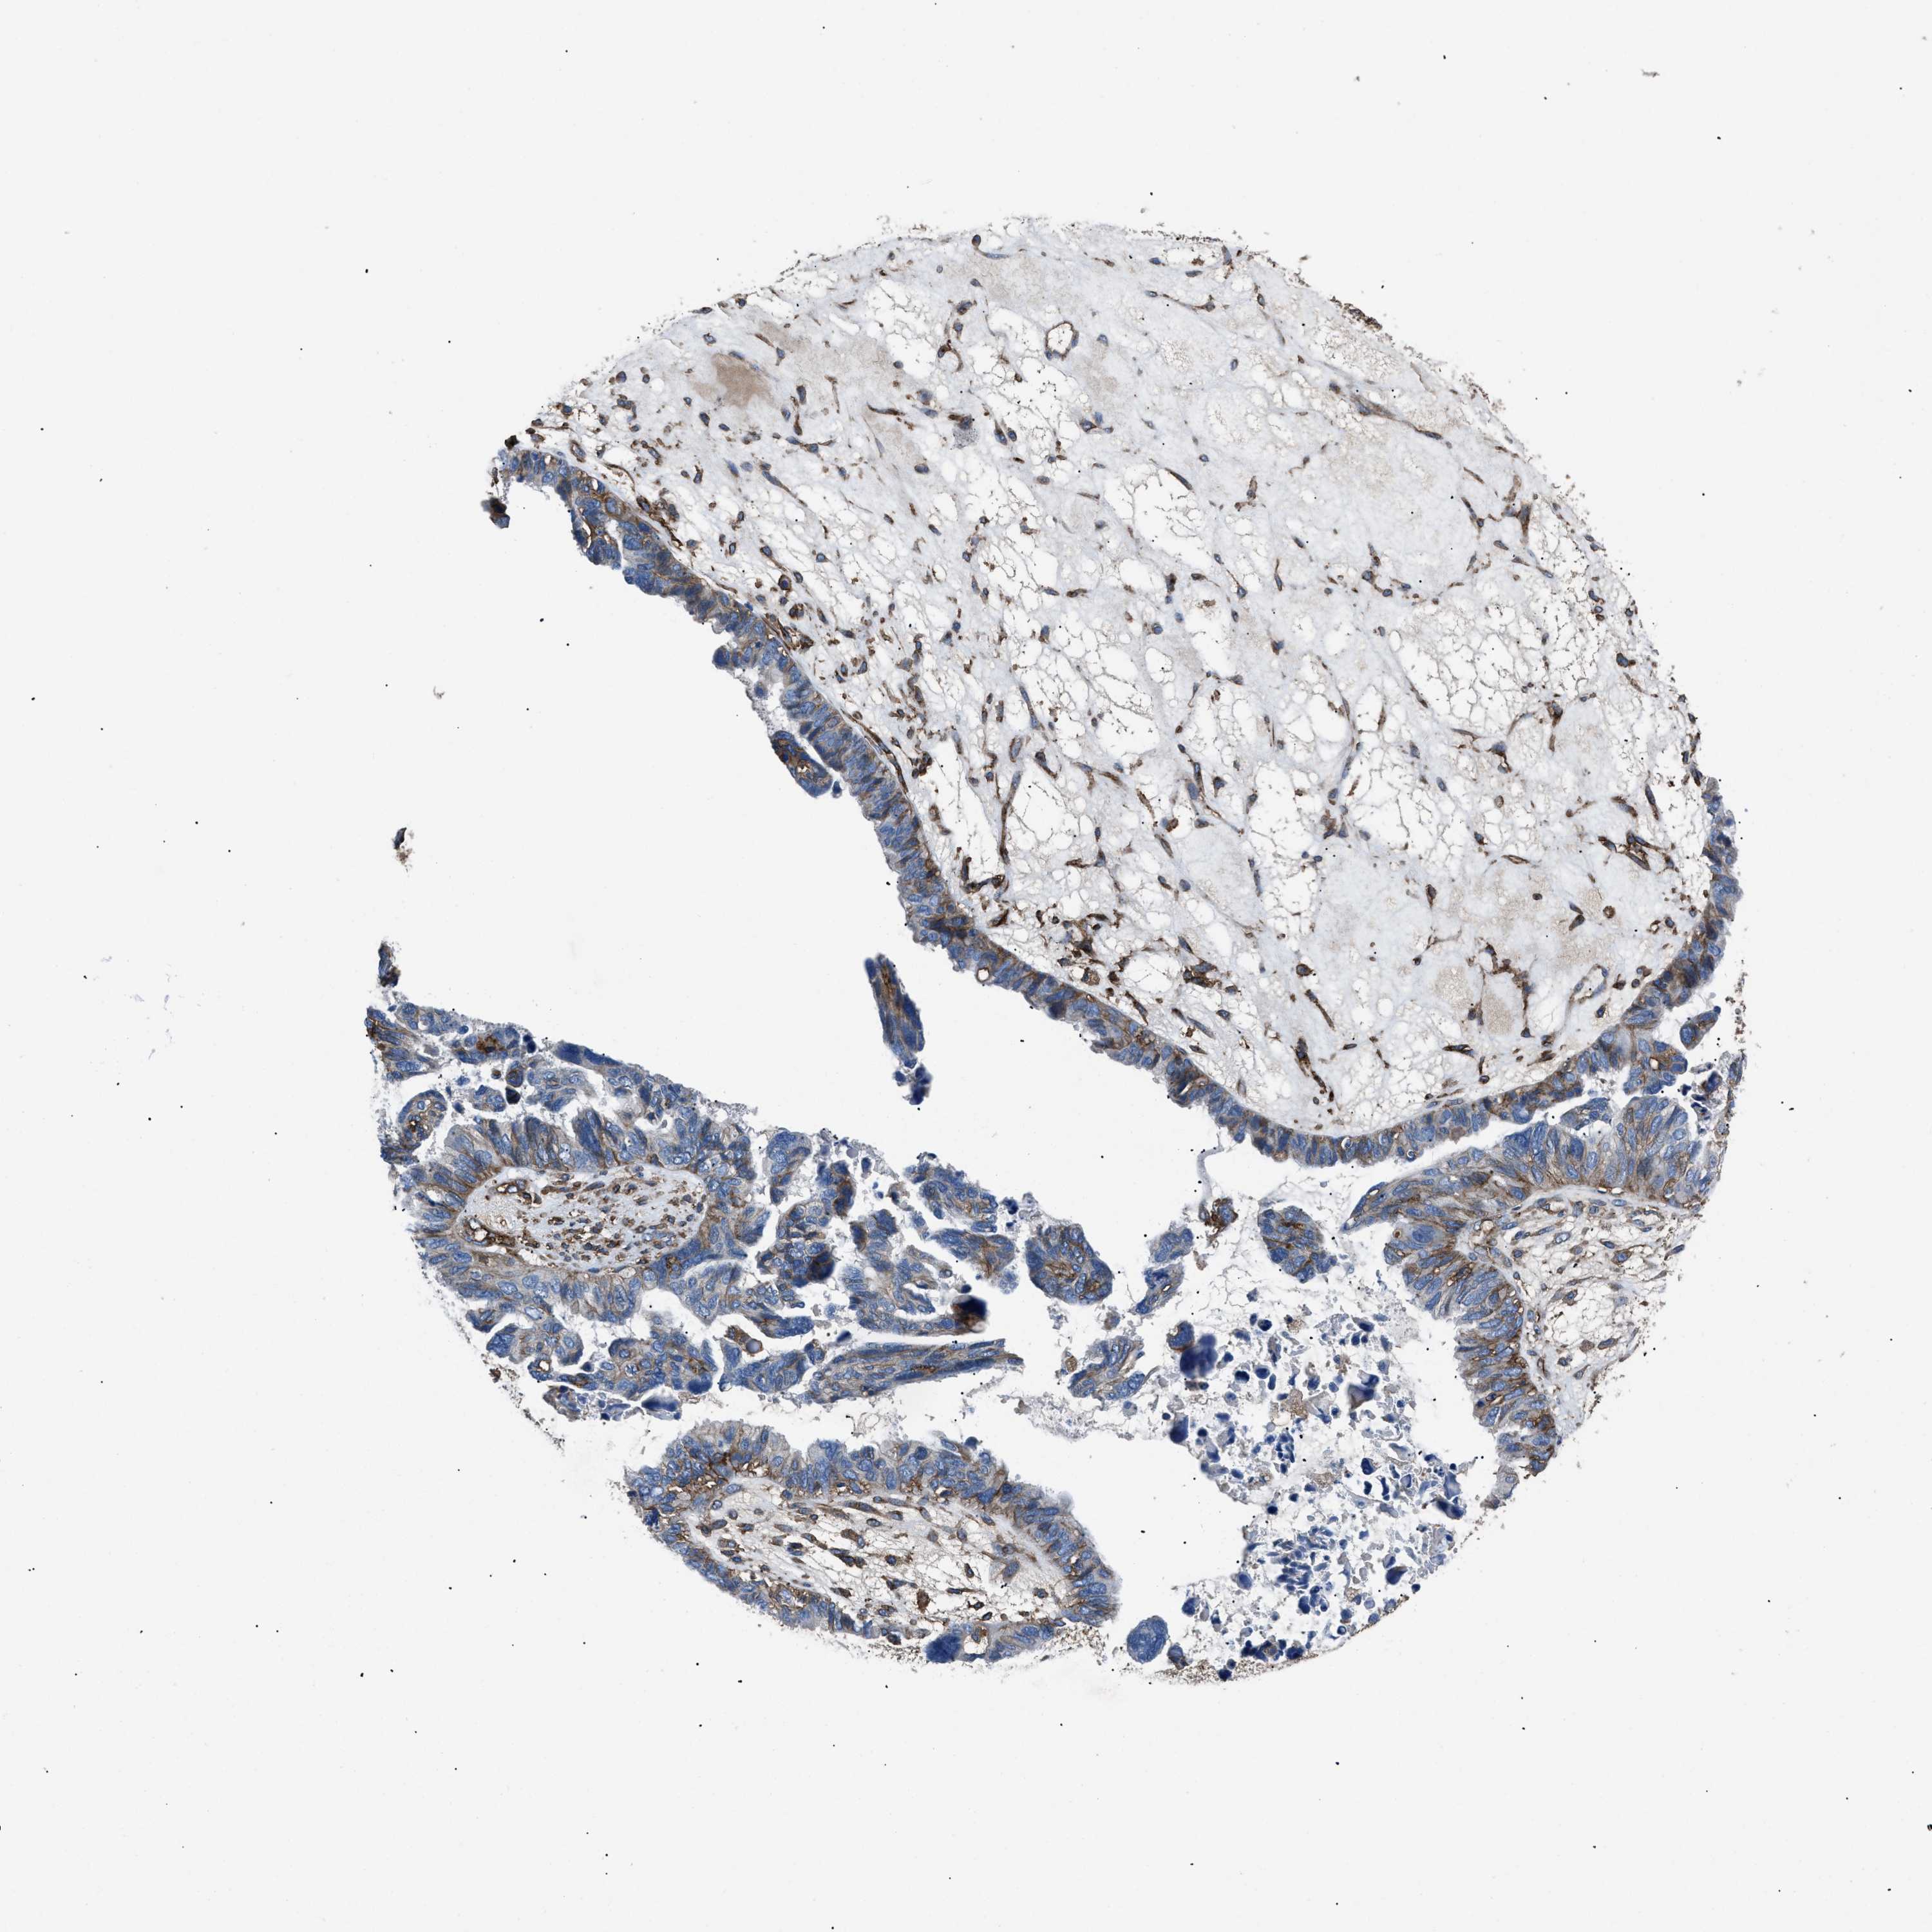

OVARIAN CANCER - Protein expressioni

A mouse-over function shows sample information and annotation data. Click on an image to view it in a full screen mode. Samples can be filtered based on level of antibody staining by selecting one or several of the following categories: high, medium, low and not detected. The assay and annotation is described here.

Note that samples used for immunohistochemistry by the Human Protein Atlas do not correspond to samples in the TCGA dataset.

Antibody stainingi

Antibody staining in the annotated cell types in the current human tissue is reported as not detected, low, medium, or high, based on conventional immunohistochemistry profiling in selected tissues. This score is based on the combination of the staining intensity and fraction of stained cells.

Each image is clickable and will lead to virtual microscopy that enables deeper exploration of all samples and also displays staining intensity scores, fraction scores and subcellular localization as well as patient and tissue information for each sample.

Antibody HPA009285

Antibody HPA017139

Antibody CAB017826

Cystadenocarcinoma, serous, NOS

Carcinoma, endometroid

Cystadenocarcinoma, mucinous, NOS

Carcinoma, NOS